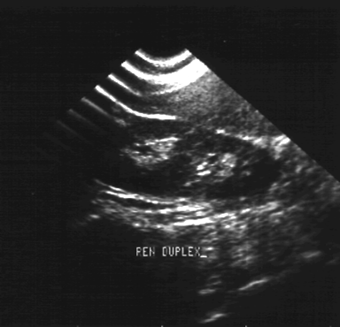

| Рис. 6.15. Сонограмма почек. Увеличение паренхимы правой почки (26 мм, двойная стрелка) и снижение ее эхогенности. Острый пиелонефрит правой почки. |